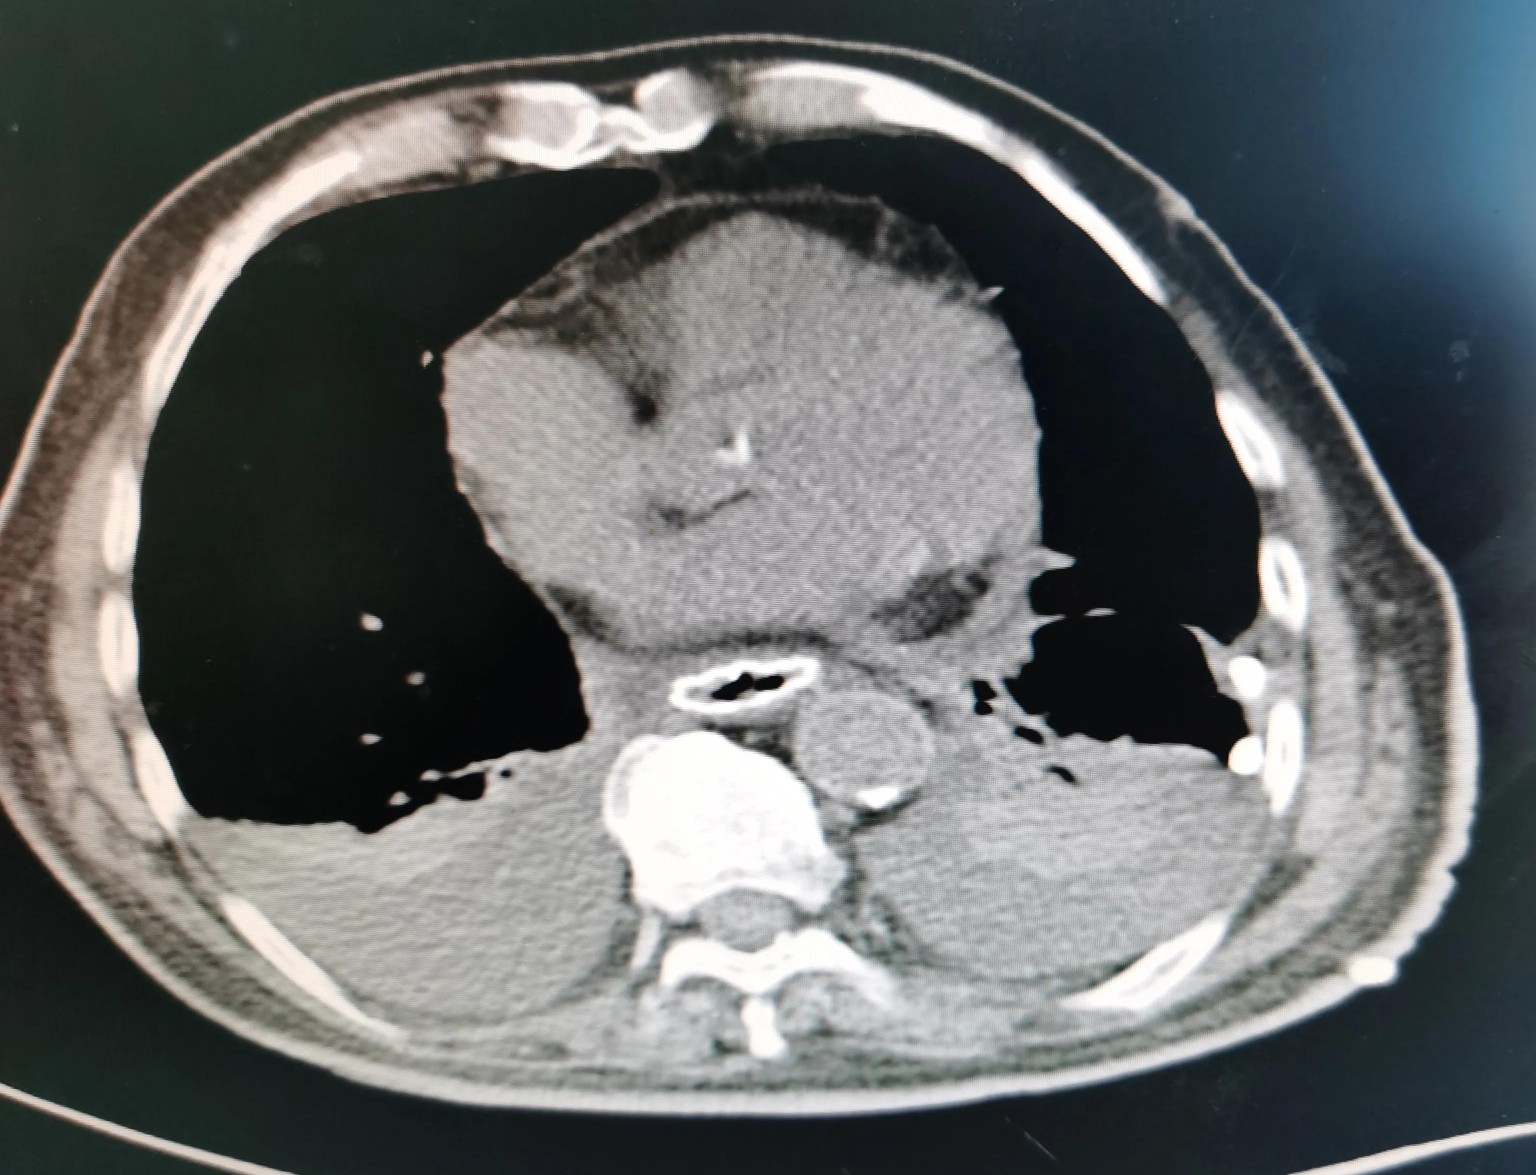

贲门部肿瘤CT表现

肿瘤旁肿大淋巴结,术后病理证实为肿瘤转移

尽管病情危重,但王老非常坦然,好像把生死看的很淡,笑看人生总是尽力积极配合治疗。王老尽管年龄很大并且做过好几次手术,但是由于平时保养的不错,看上去偏年轻,并且住院后各种检查发现除心脏功能差一点,其它器官功能还可以。化验检查肿瘤标记物甲胎蛋白(AFP)特别高,超过9000ng/ml,考虑是种特殊类型的贲门癌,血色素63g/l,并且胃管里仍时有鲜血引出,腹部CT检查食管下段及贲门区占位,邻近淋巴结肿大,较上次检查明显增大,考虑为转移。因为病情重,连个增强CT都没敢做。